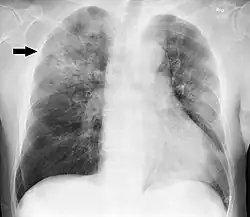

| Chest X-ray of a pneumonia caused by influenza and Haemophilus influenzae, with patchy consolidations, mainly in the right upper lobe (arrow) | |